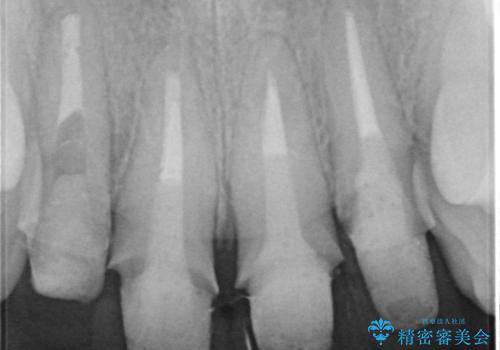

- 「黒ずんで、見栄えの悪い前歯をきれいにしたい。」と、前歯のセラミック治療を希望され来院されました。

全て根管治療のすでになされている歯の変色で、オールセラミッククラウンによる審美性の改善を計画します。